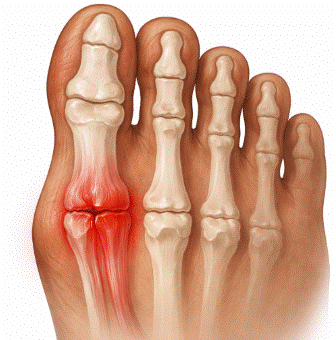

Fractura de estrés del metatarsiano: biomecánica y prevención

La fractura de estrés del metatarsiano es una lesión por sobrecarga frecuente en deportistas, militares y cualquier persona sometida a un aumento brusco de la carga de impacto sobre el pie, y su incidencia ha crecido de forma paralela al auge del running y los deportes de alta demanda física. A diferencia de las fracturas […]